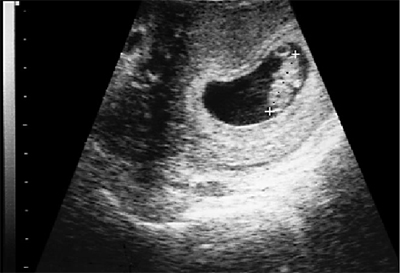

Зачем проводить УЗИ-исследование на 8 неделе беременности?

Этот период для ребенка характеризуется заключительной стадией эмбриона. За 2 месяца вынашивания сформированы все главные внутренние органы малыша, дальше они будут расти и развиваться....